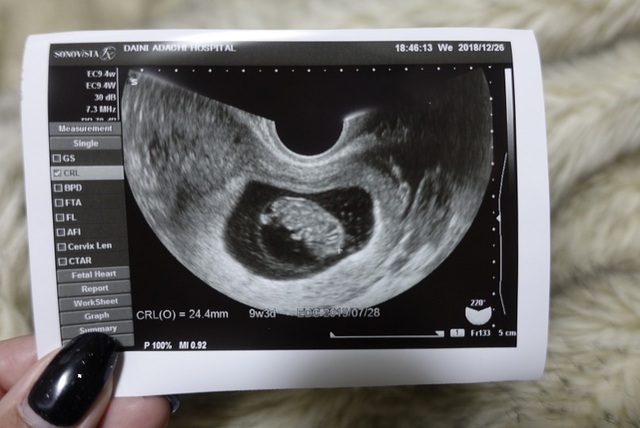

9週6日(9w6d・女の子)|こりす☆ さん(32歳)

エコー写真撮影時のエピソード:

初めて検査をしに行きました。 12月は仕事が忙しく疲れからなのか、悪阻なのかわからない症状があり不安でした。

お腹にいる事がわかり主人と喜び、忙しい中ちゃんと育ってくれて本当にうれしかったのを覚えています。